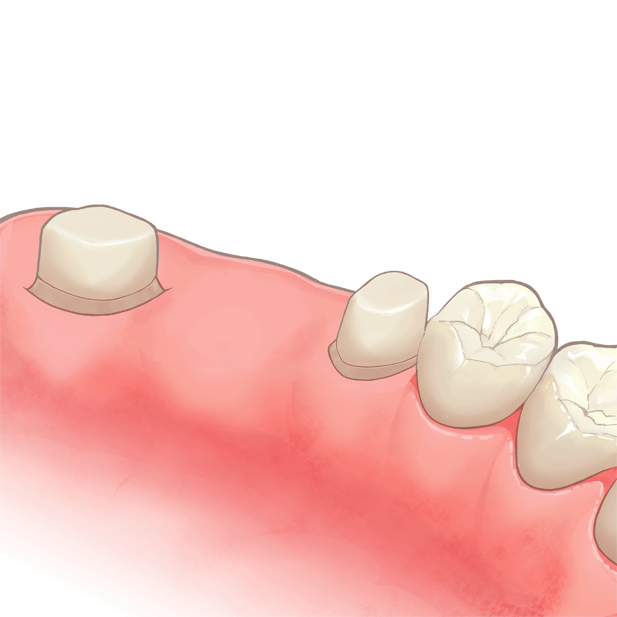

装着後